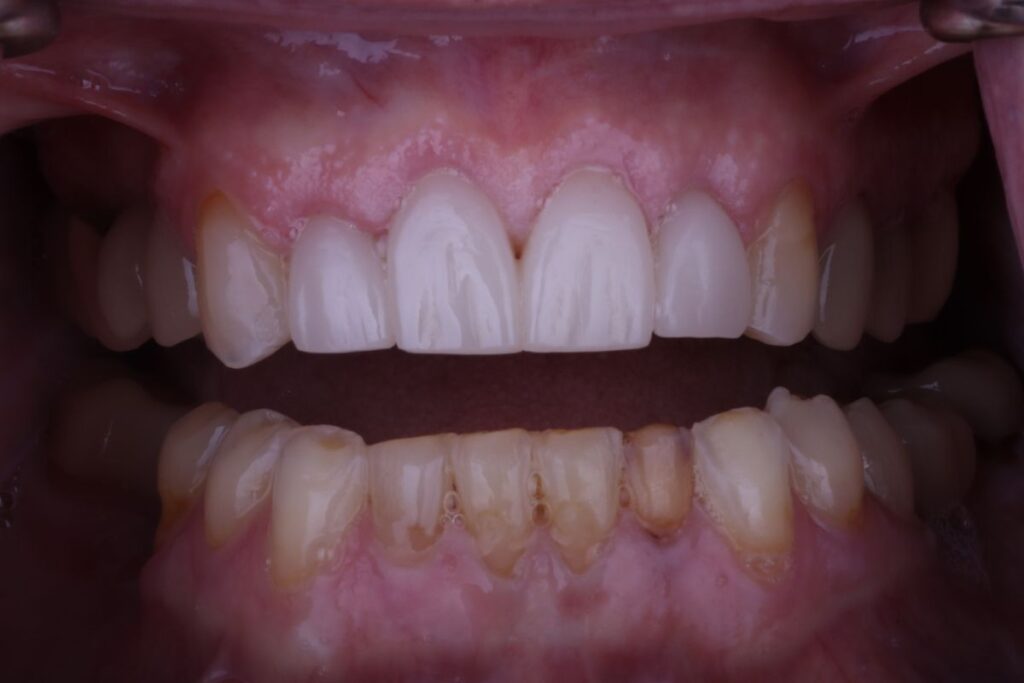

Astounding Results

The results of Bryon’s treatment were nothing short of transformative. The new crowns corrected his bite and gave him a smile he could be proud of. Bryon, who had previously been embarrassed to show his teeth, now beams confidently. His new smile has restored his true, authentic self—happy, outgoing, and unafraid to share his joy with the world.

Dr. Perry shared, “This patient has been a long-term loyal customer to us throughout the years. He had been wanting to fix his front teeth for quite a while but had a hard time trusting a doctor to do the work. I am so happy he trusted me, and we could not be more ecstatic about the results. He is smiling again, and the confidence in his smile just shines.”

Bryon himself couldn’t be happier with the outcome. He expressed, “I am so happy Dr. Perry gave me my smile back. I no longer have to hold back my smile, and I can be myself again.”